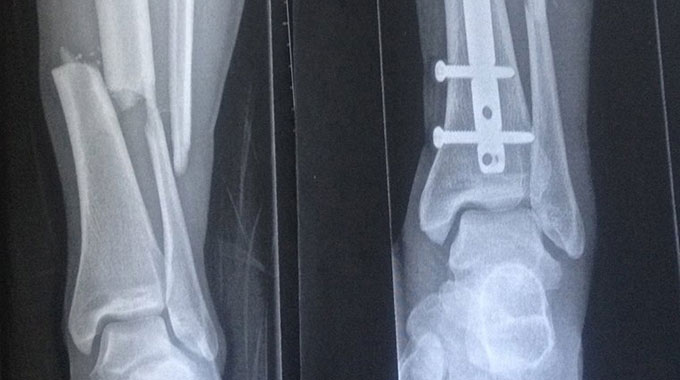

Bei einem Unfall am vergangenen Mittwoch in Saas Fee hat sich Isabel Derungs das Schien- und das Wadenbein gebrochen. Die schweizer Slopestylerin hatte hierbei unglaublich großes Pech.

Während des Trainings in Saas-Fee fuhr Derungs mit dem Schlepplift. Vor ihr stürzte ein Wintersportler und rutsche die vereiste Liftspur hinab in sie hinein. Derungs wurde umgehend ins Krankenhaus gebracht und operiert. Eine Teilnahme beim freestyle.ch kommt für die Sotschi-Achte nicht mehr in Frage.